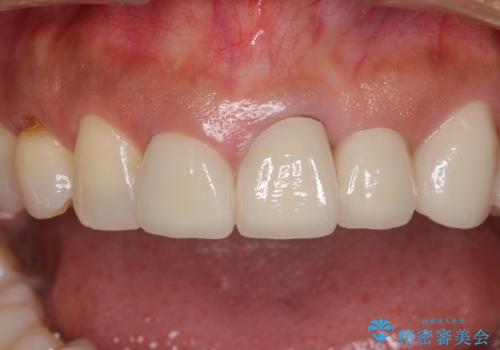

- 前歯の歯肉の高さが左右で異なっていることを気にして来院された患者様です。

歯肉レベルを調整するために歯周外科処置をおこない、その後にオールセラミッククラウンにて補綴することとしました。

歯肉の位置を整えるには歯周外科処置が必要であると説明した際には、なかなか踏み切ることができず、大変悩まれていました。

処置後の痛みはあまり気にならず、歯肉位置の左右差もほとんどなくなり、患者様には大変満足していただきました。